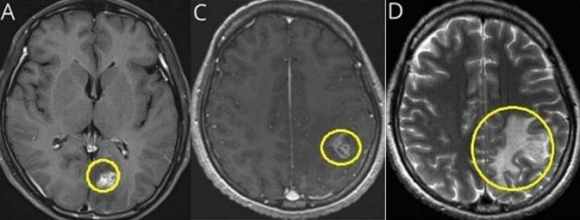

초기 뇌 MRI에서 좌측 후두엽에 조영증강된 종괴가 관찰된 모습. 8개월 뒤 다시 촬영한 뇌 MRI에서 좌측 두정엽에 새롭게 조영증강된 종괴의 모습. 좌측 두정엽 종괴 주변에 심한 뇌부종이 동반된 모습. 사진=서울대병원

7개월 후, 환자는 극심한 두통과 전신 발작으로 병원을 다시 찾았다. 추가 MRI 검사에서는 병변이 좌측 두정엽으로 이동한 것이 확인됐다. 병변이 이동하는 점은 기생충 감염의 대표적인 진단 단서로, 의료진은 효소결합면역흡착검사(ELISA)를 통해 스파르가눔증 항체를 확인했다.